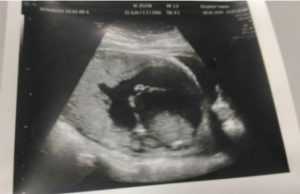

Berkongsi pengalaman, Sharifah Nuratiqah Syed Abdul Rahim berkata, dia kehilangan cahaya matanya ketika usia kandungan masing-masing berusia 19 minggu pada 2016, 21 minggu (2018) dan 22 minggu (2019).

Wanita berusia 35 tahun itu memberitahu, kehilangan itu disebabkan dirinya mengalami masalah pangkal rahim yang lemah, yang menyebabkan kelahiran bayi pramatang.